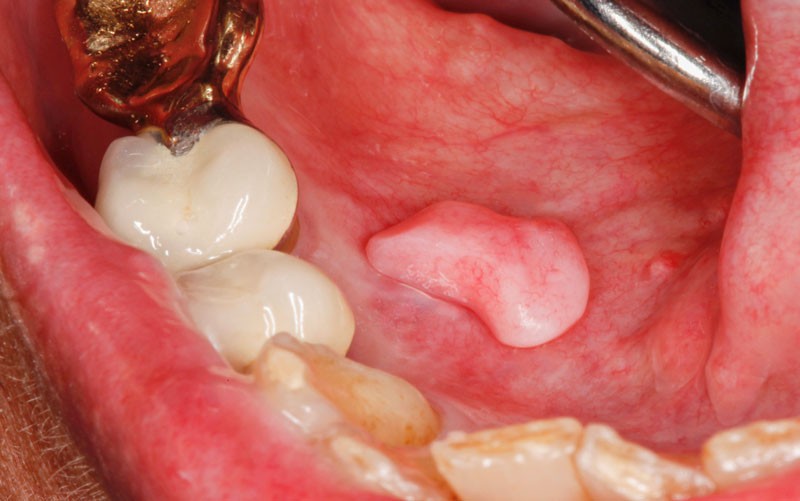

Sur le plancher buccal antérieur droit, on observait une tumeur pédiculée, oblongue, de 9 x 5 x 4 mm, de consistance élastique. Elle implantait au centre du plancher du plancher buccal antérieur droit. Devant ce tableau clinique, il n’était guère possible d’évoquer un diagnostic.

L’examen histopathologique de la pièce d’exérèse a montré qu’il s’agissait d’un nodule revêtu d’un épithélium malpighien, parakératinisé, mince, avec des crêtes épithéliales raccourcies, focalement absentes. Son centre était constitué par du tissu conjonctif fibreux dense, contenant des vaisseaux à paroi fine. On notait la présence en un point d’un petit amas de lymphocytes qui pénétraient les assises épithéliales profondes. Cet aspect était assez caractéristique d’un nodule d’hyperplasie fibro-épithélial de grande taille et de localisation inhabituelle.